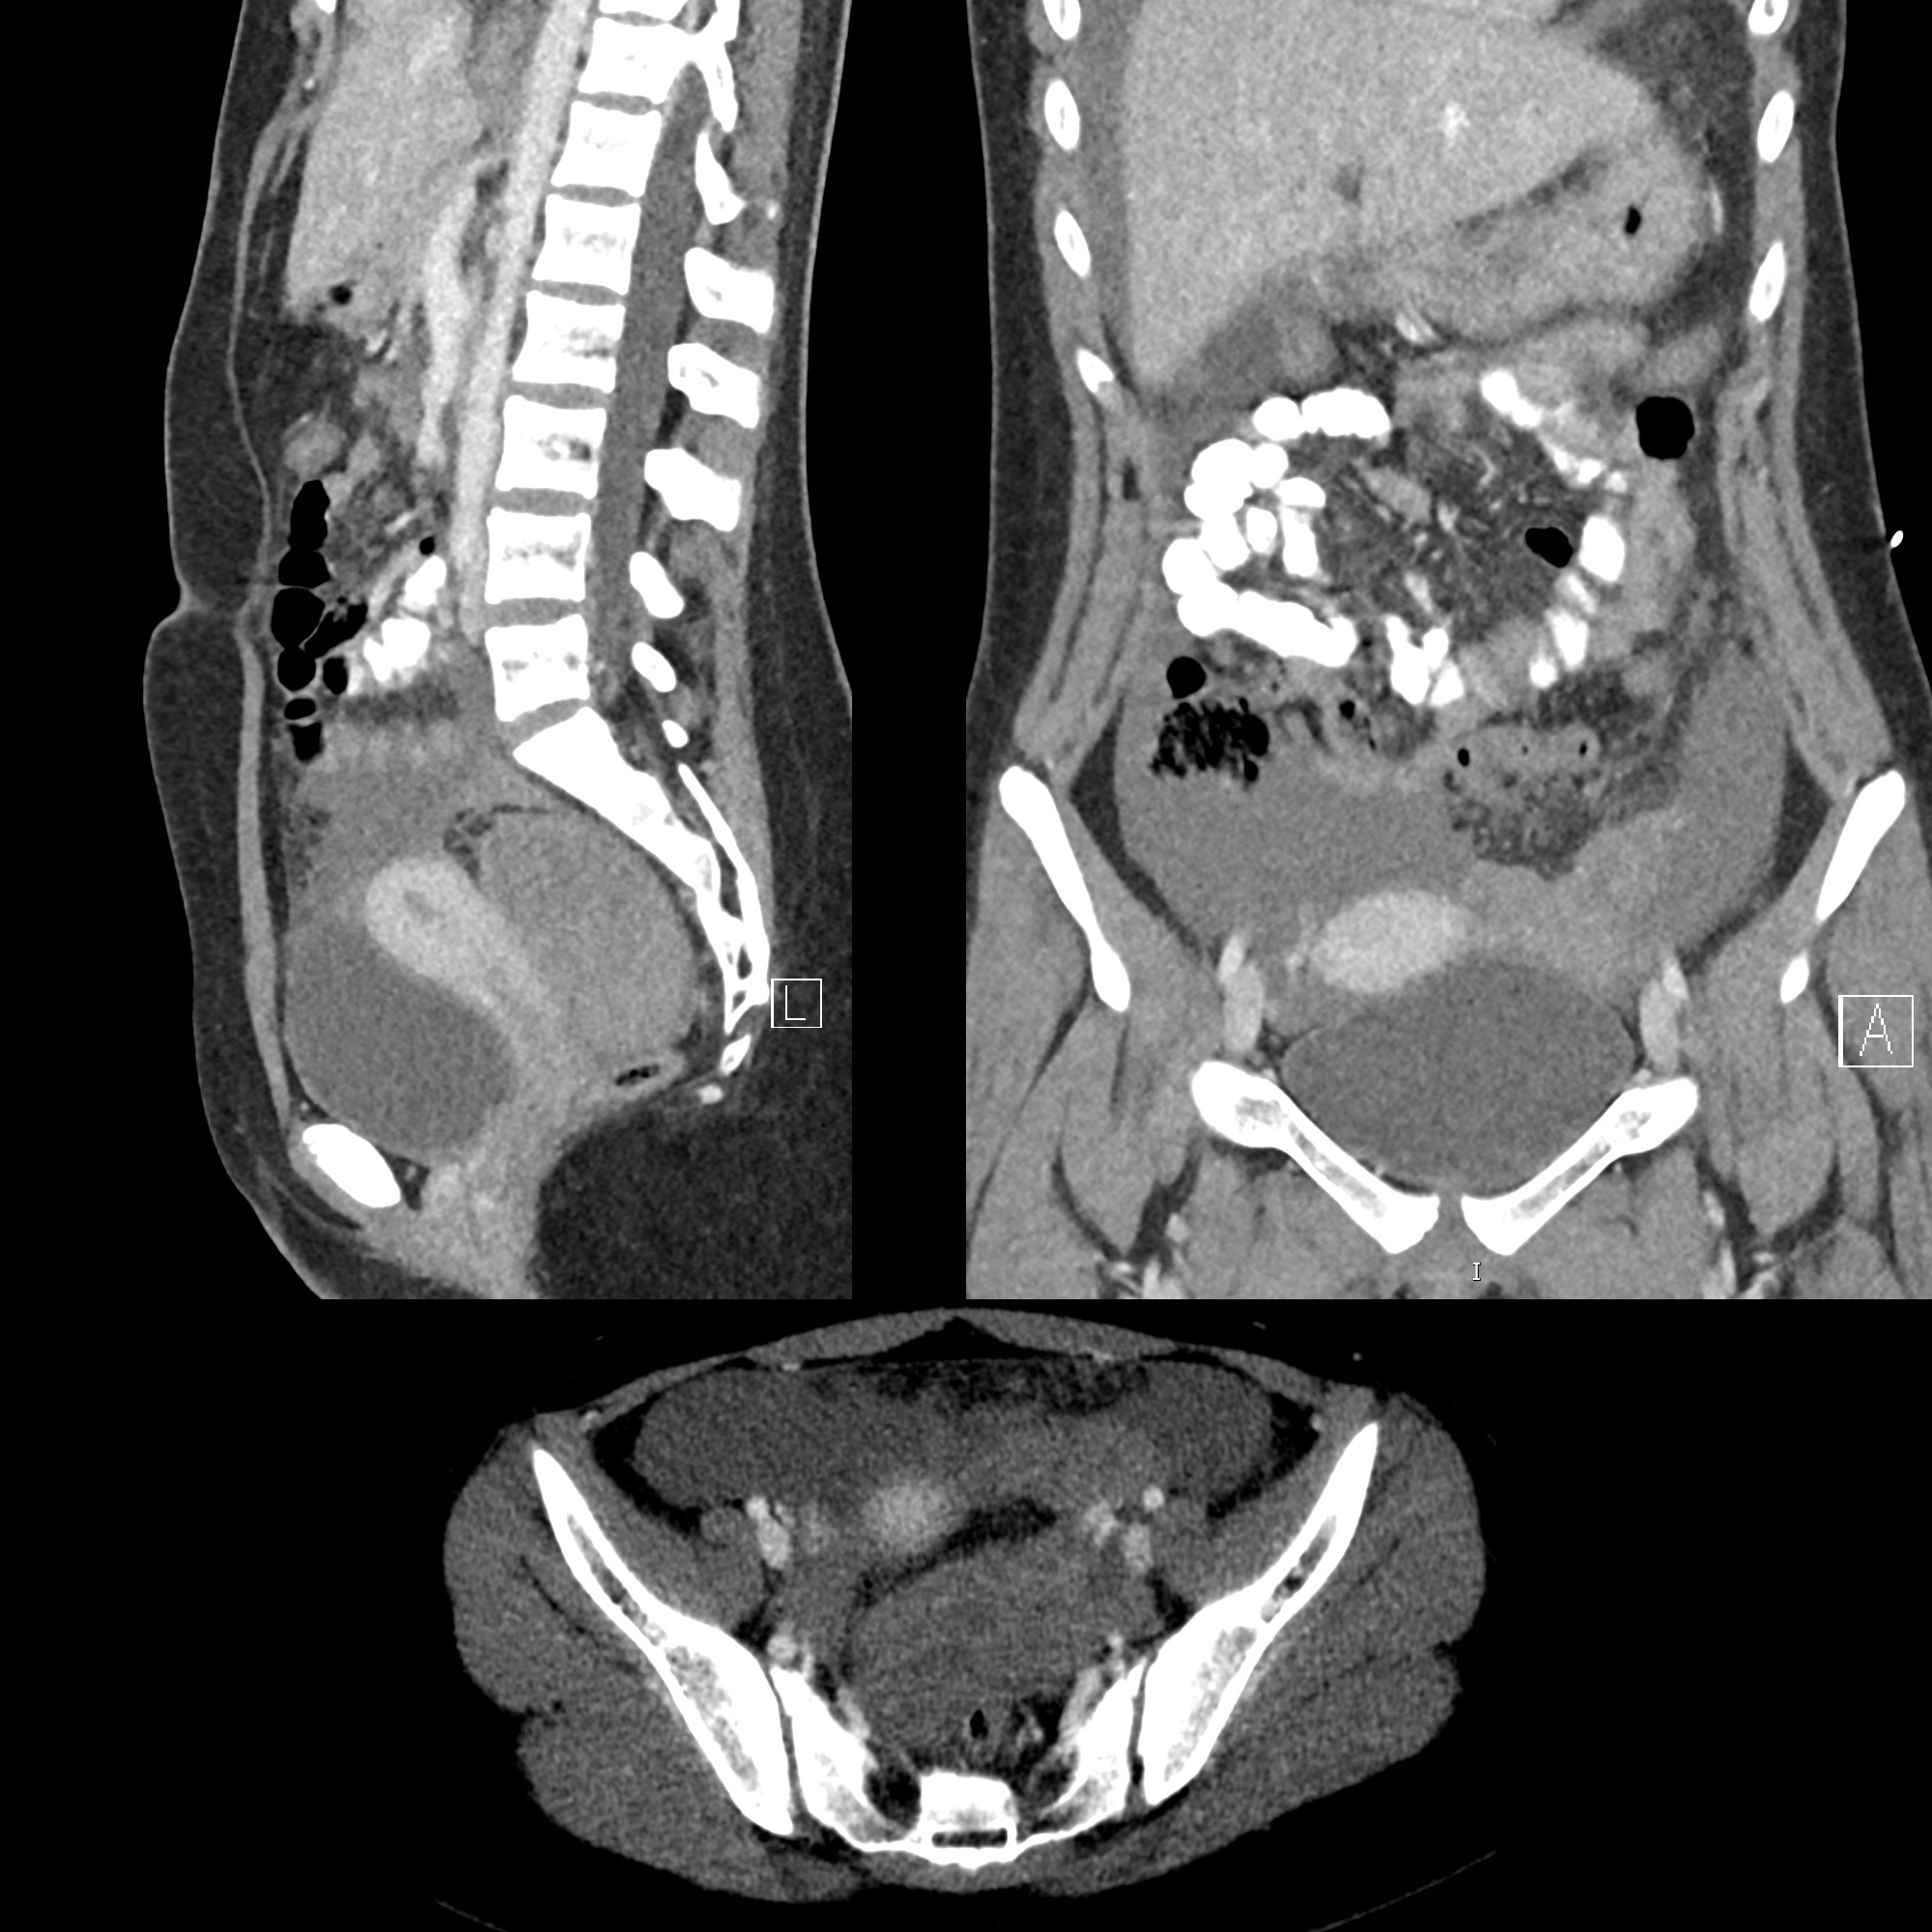

Pediatric Ectopic Pregnancy | Pediatric Radiology Reference Article ...

2000 × 2000 px July 19, 2025 Ashley Learning